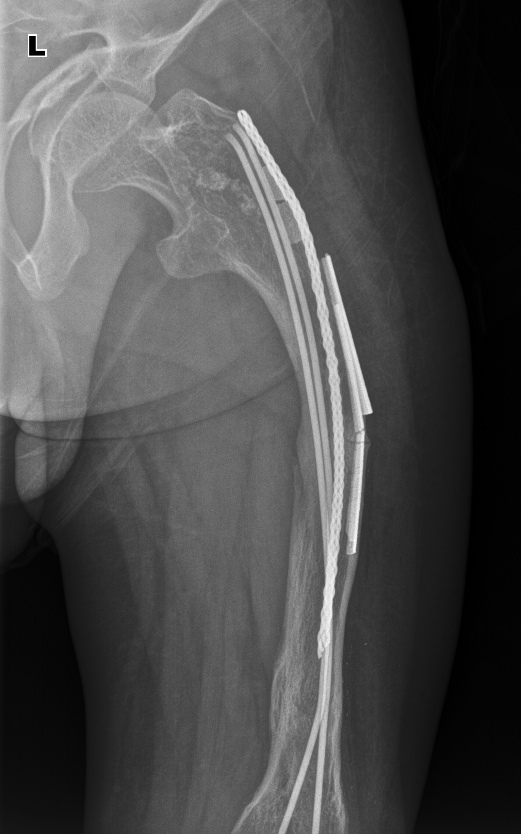

Ребенок, 8 лет, надвертельный перелом шейки левой бедренной кости. Установлены 4 спицы, фиксирующие перелом.